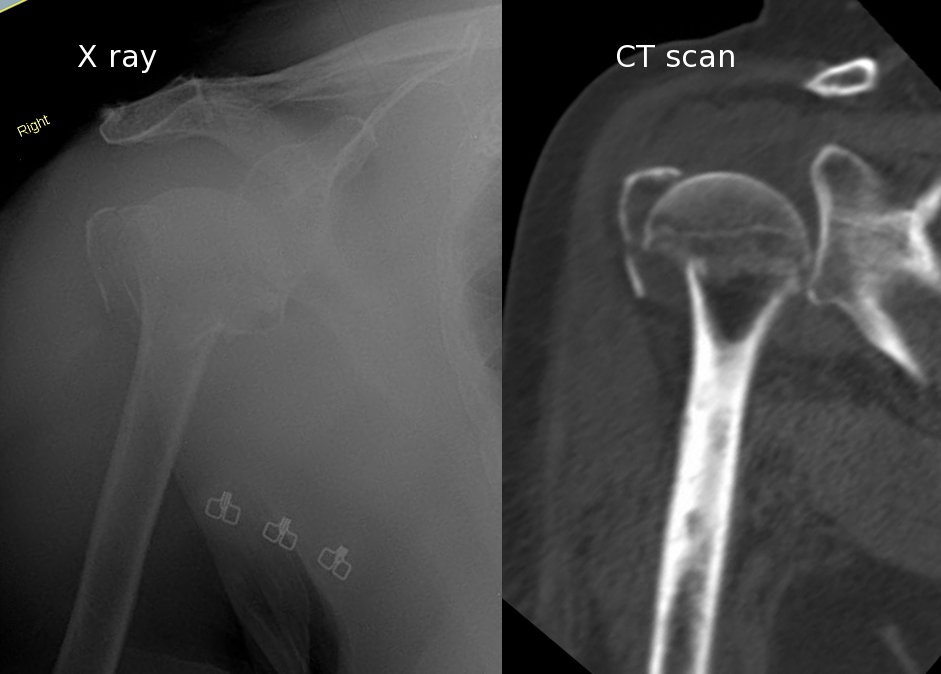

The xrays below are from a patient with left sided rotator cuff arthropathy. Patient presented with chronic shoulder pain and difficulty raising arm.

In cases of comminuted proximal humerus fractures, osteosynthesis with plate and screws has a higher likelihood of failure, and hemiarthroplasty (partial replacement) has been the historical alternative treatment. The problem with hemiarthroplasty in fracture cases is this: the rotator cuff tendon often does not heal to the artificial prosthesis. Therefore, in recent years *reverse replacement** has become the solution to this problem, albeit not a perfect solution.